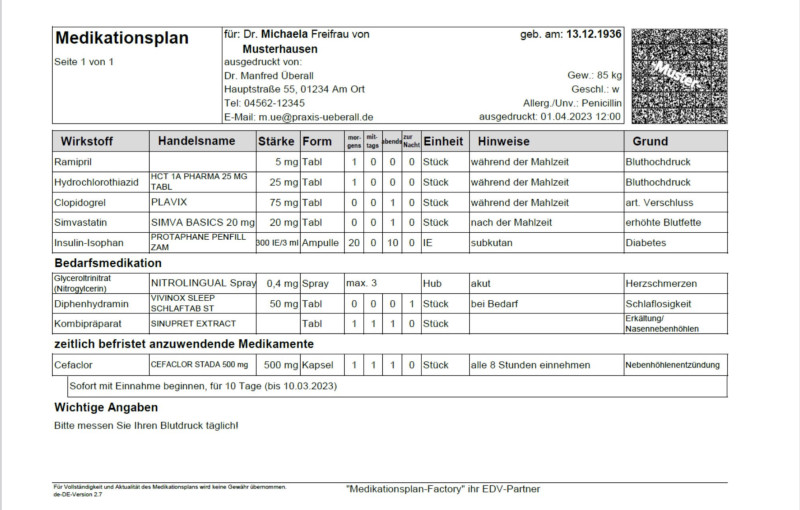

Kombination aus PREVENT und CAC verbessert die Vorhersagekraft

Mit dem PREVENT-Rechner kann das 10- und 30-Jahres-Risiko für ein kardiovaskuläres Ereignis abgeschätzt werden. Einer neuen Studie zufolge schließt ein niedriger PREVENT-Score eine subklinische Atherosklerose jedoch nicht aus. Hier braucht es den CAC-Score für eine Prognose zu zukünftigen kardiovaskulären Ereignissen.